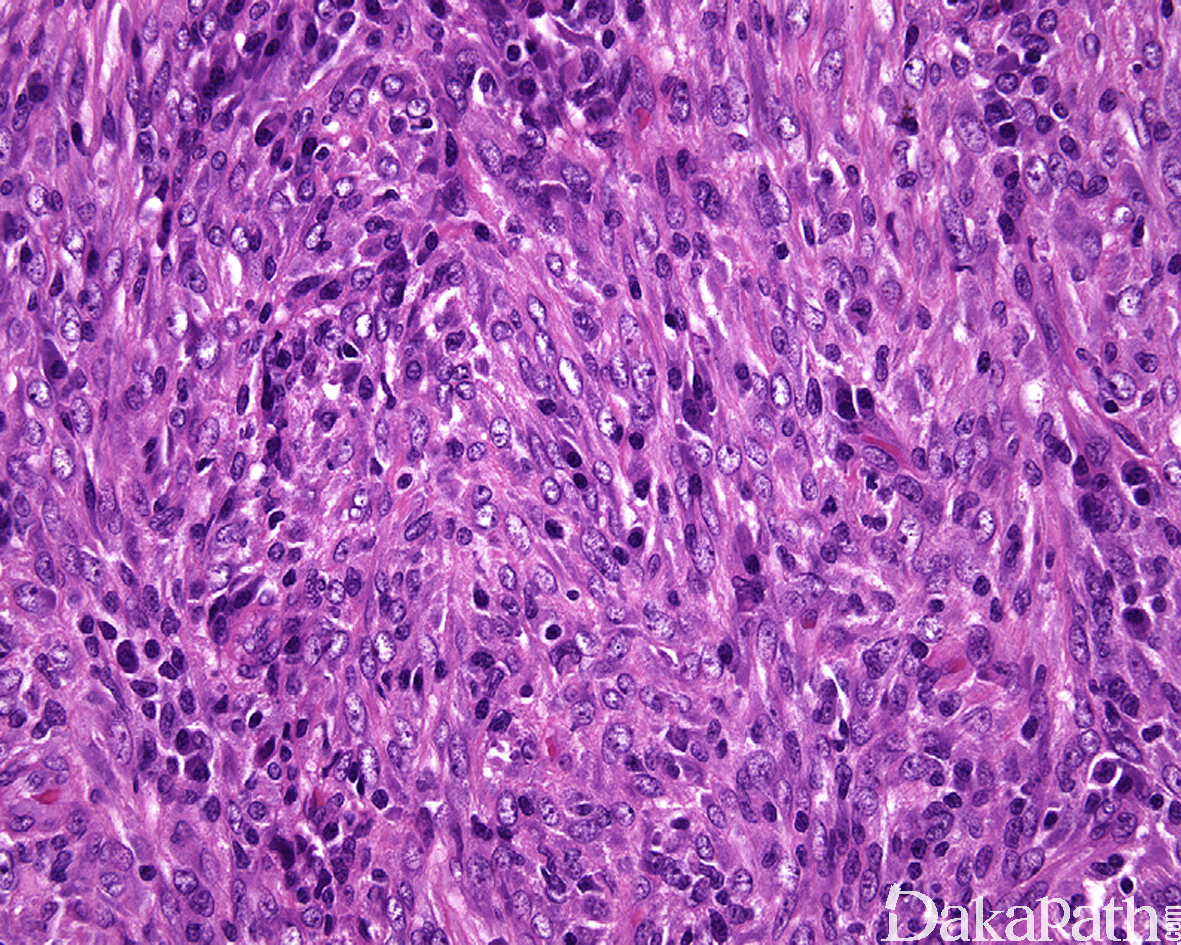

组织学上,IMT 由比例多少不等的梭形或多角形细胞、纤维/肌纤维母细胞以及淋巴浆细胞混合性组成,部分病例可见嗜酸性粒细胞和中性粒细胞浸润;

梭形细胞可见致密的席纹状或束状排列仅见少量的炎细胞浸润,亦可表现为广泛的炎性背景仅有少数梭形肿瘤细胞;

梭形瘤细胞通常具有卵圆形至伸展的核,小而显著的嗜酸性核仁以及较丰富的双嗜性胞浆,有时候类似于萎缩的横纹肌细胞或神经节细胞;

根据病变时限的长短,IMT 可显示一系列谱系的形态学改变包括相对温和和少细胞的硬化性病变至更富于细胞和伴有非典型性的病变,有时可以某种形态学为主,亦可同时出现在同一病变内;

核分裂象多少不等,但通常较少,罕见坏死;